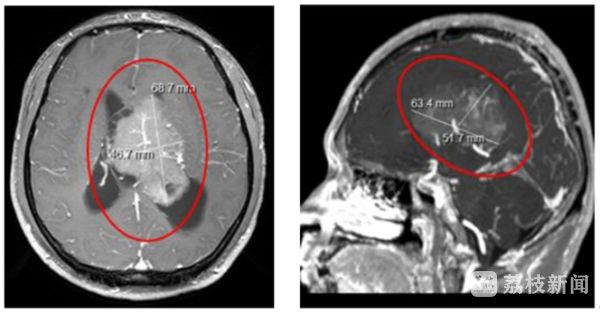

突如其来的变故,让全家人陷入惊慌。肿瘤生长在小刘大脑中线部位脑室内,直径有7厘米左右,和拳头差不多大,已严重影响脑脊液循环,如不及时开展手术进行切除,随时可能突发脑疝造成昏迷引发生命危险。常州市第一人民医院神经外科邵耐远主任医师立即将刘先生收治入院,并完善相关检查。

邵耐远医生介绍说,脑室位于脑内深部,结构复杂,临近重要神经、血管。加上肿瘤巨大,与周围的丘脑、脑干以及一些重要结构都有黏连,同时血供异常丰富,手术难度非常大,稍有不慎,就会导致偏瘫、昏迷等严重神经功能障碍的并发症,这对医生是一个很大的挑战。“肿瘤巨大且血供丰富,隐藏在大脑深部、脑室的中央,而且供血动脉都在深部,常规方法切除肿瘤可能要出血800-1000ml,术中将面临很大的困难。如果术前进行肿瘤栓塞,可以大大减少出血,有利于切除肿瘤并保护好周围重要结构。”